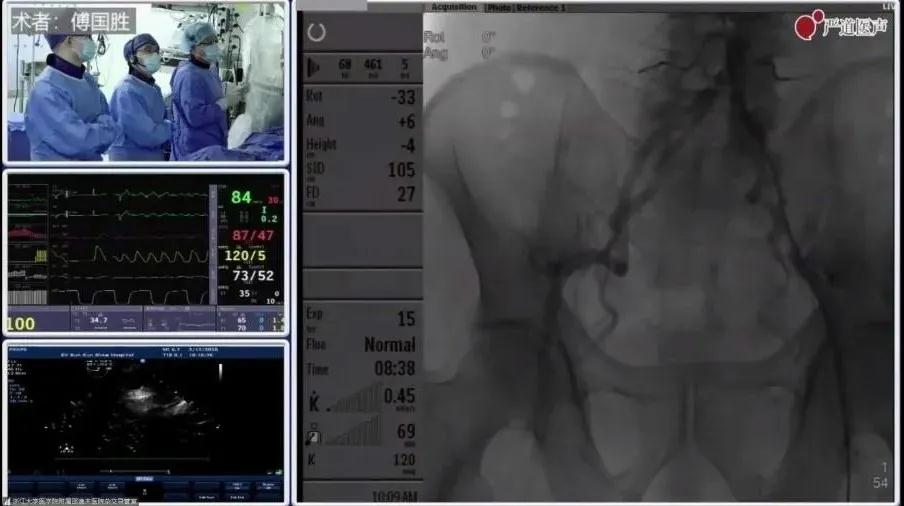

在第15届“西子心血管联席会议”期间,大会主席、浙江大学医学院附属邵逸夫医院傅国胜教授带来了一场精彩的TAVR教学手术演示。

傅国胜教授TAVR团队手术演示

手术过程

穿刺置管:右侧颈内静脉穿刺6F鞘管置入,临时起搏电极送入右心室,测试成功后备用;左侧股动脉穿刺6F鞘管置入,送入猪尾导管到腹主动脉远端造影,确定右股动脉穿刺位置。

左股动脉造影